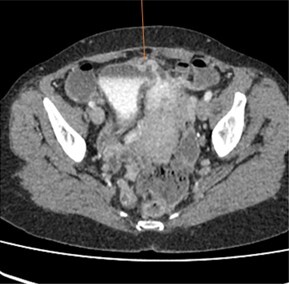

A contrast-enhanced CT scan (Figures 1 & 2) revealed a bladder tethered to the uterus with a diverticulum exhibiting irregular wall thickening and enhancement along its anterior-superior aspect. Subsequently, a 0.5 g bladder tissue, including the lesional area was resected during TURBT procedure. Her past medical history includes three caesarean sections, one complicated by an incidental bladder injury. She denies smoking, occupational chemical exposure, pelvic radiotherapy, chronic catheter use, anticoagulant therapy, nephrolithiasis apart from the noted calculus, recurrent gross haematuria outside infection or systemic diseases and there is no family history of urological malignancy.